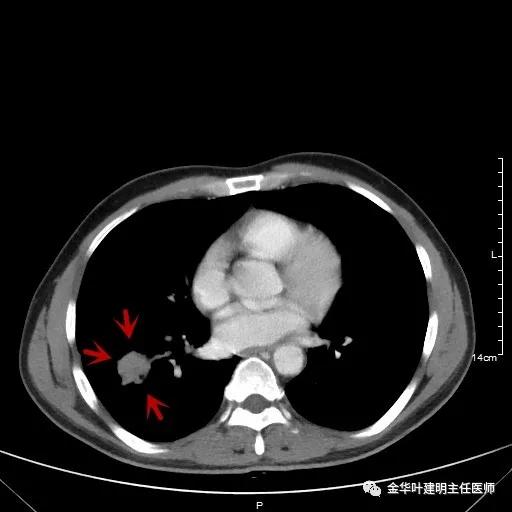

如果选取肿瘤所在的层面来看,则是以下图像:

以上是肺窗,见右肺下叶实性占位,有毛刺、浅分叶、膨胀性,血管征等,是较为典型的恶性肿瘤。

以上为纵隔窗,可见纵隔内未见显著增大的转移性淋巴结。